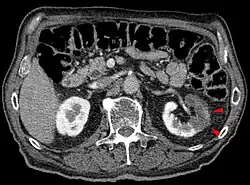

| CT scan of the abdomen showing partial infarct of the left kidney. | |